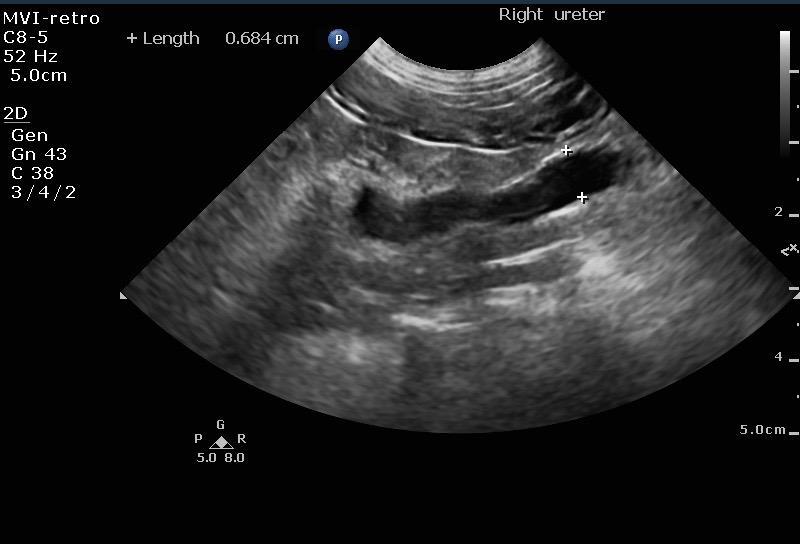

Mild pyelectasia was noted in the left kidney at 4.62 cm and pyelectasia is at 1.01 cm. The left kidney presented a slight amount of perinephric free fluid suggestive for inflammation. Right kidney presented moderate pyelectasia 1.35 cm with obstructed proximal ureter calculus 0.5 cm. Right kidney measured 5.36 cm.

The urinary bladder and trigone presented normal wall thicknesses with anechoic urine and normal tone. Pelvic urethra was imaged 3 cm beyond the cystourethral junction. No uroliths or sediment were visualized. No evidence of inflammatory or neoplastic changes were noted. Left ureter in this patient presented 0.7 cm calculus and a separate 0.25 cm calculus obstructive the left ureter midway between the kidney and the bladder.